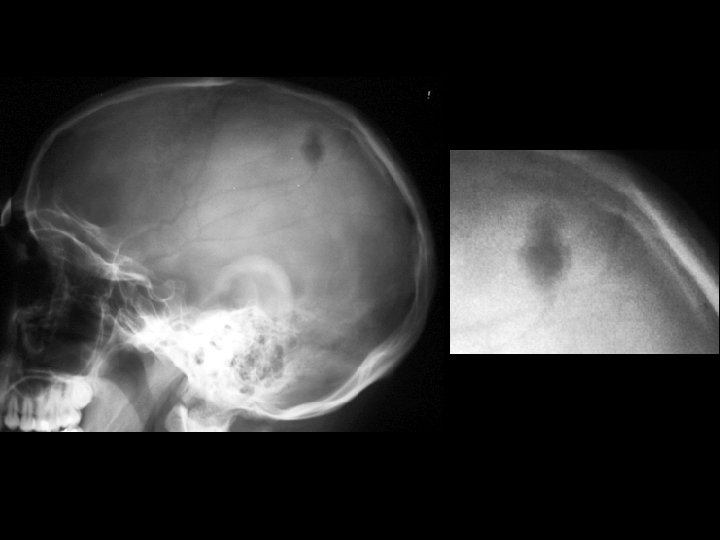

Langerhan’s cell histiocytosis • Findings: – Single geographic lytic lesion of the skull involving inner and outer table – No sclerotic margin but surrounding sclerotic reaction • ddx: – Metastasis – Osteomyelitis – Multiple myeloma (multiple) – Epidermoid (sclerotic rim)